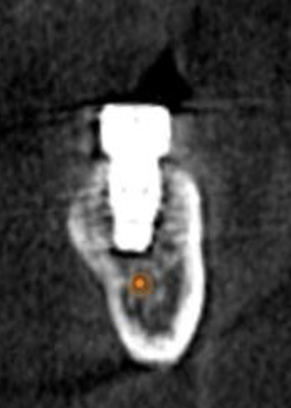

(3.) CBCT scan of tooth No. 12, exhibiting a retained root that previously received root canal treatment.

Figure 3